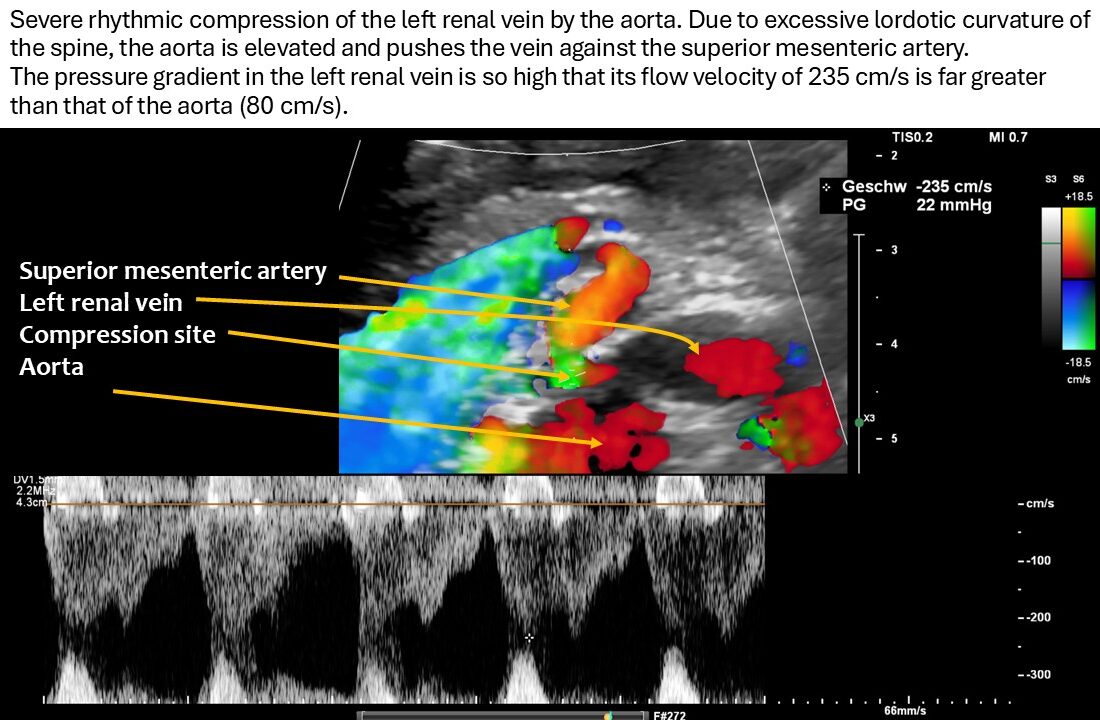

As a result of the pronounced lordosis and the associated ventral displacement of the aorta, the left renal vein is also severely compressed.

The narrowest point is located at the arcuate origin of the right renal artery. The lumen of the renal vein is barely recognizable. As a result, there is a significant acceleration of flow from 14 cm/s to the left of the aorta to 235 cm/s at the narrow point. This is a severe hemodynamically significant outflow obstruction of the left kidney, often somewhat misleadingly referred to as nutcracker syndrome. This constellation is responsible for the pain radiating from the epigastrium to the left hypochondrium. As the stomach fills, the compression exerted by the greater curvature on the tense renal vein intensifies the discomfort in the epigastrium. The left renal vein runs relatively far cranially.

The systolic flow velocity in the abdominal aorta is only 80 cm/s. This indicates the compliance of the aortic vessel wall. However, in the celiac trunk, there are significantly increased flow velocities that vary with breathing, namely 161 cm/s in the middle respiratory position, 287 cm/s during inspiration, and 210 cm/s during expiration. This indicates ligamentum arcuatum syndrome, whose typical symptoms are vegetative symptoms such as nausea, circulatory dysregulation, disturbed peristalsis, sudden skin redness, and loss of appetite, as well as, of course, severe postprandial epigastric abdominal pain—the patient’s main symptom.